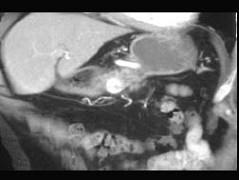

选项 A、典型症状是清晨自发性低血糖 B、是胰腺内分泌肿瘤中最常见的 C、绝大多数是恶性肿瘤 D、单发肿瘤占90%以上 E、给予葡萄糖或进餐后症状缓解

答案 C